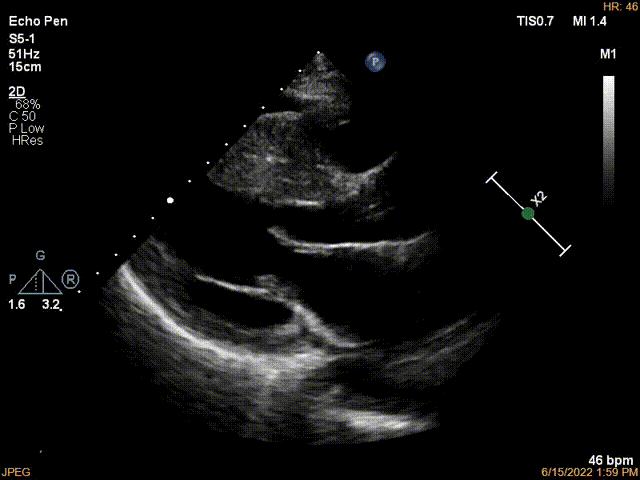

经食管超声显示室间隔明显肥厚, “SAM”征阳性, “自杀”二尖瓣